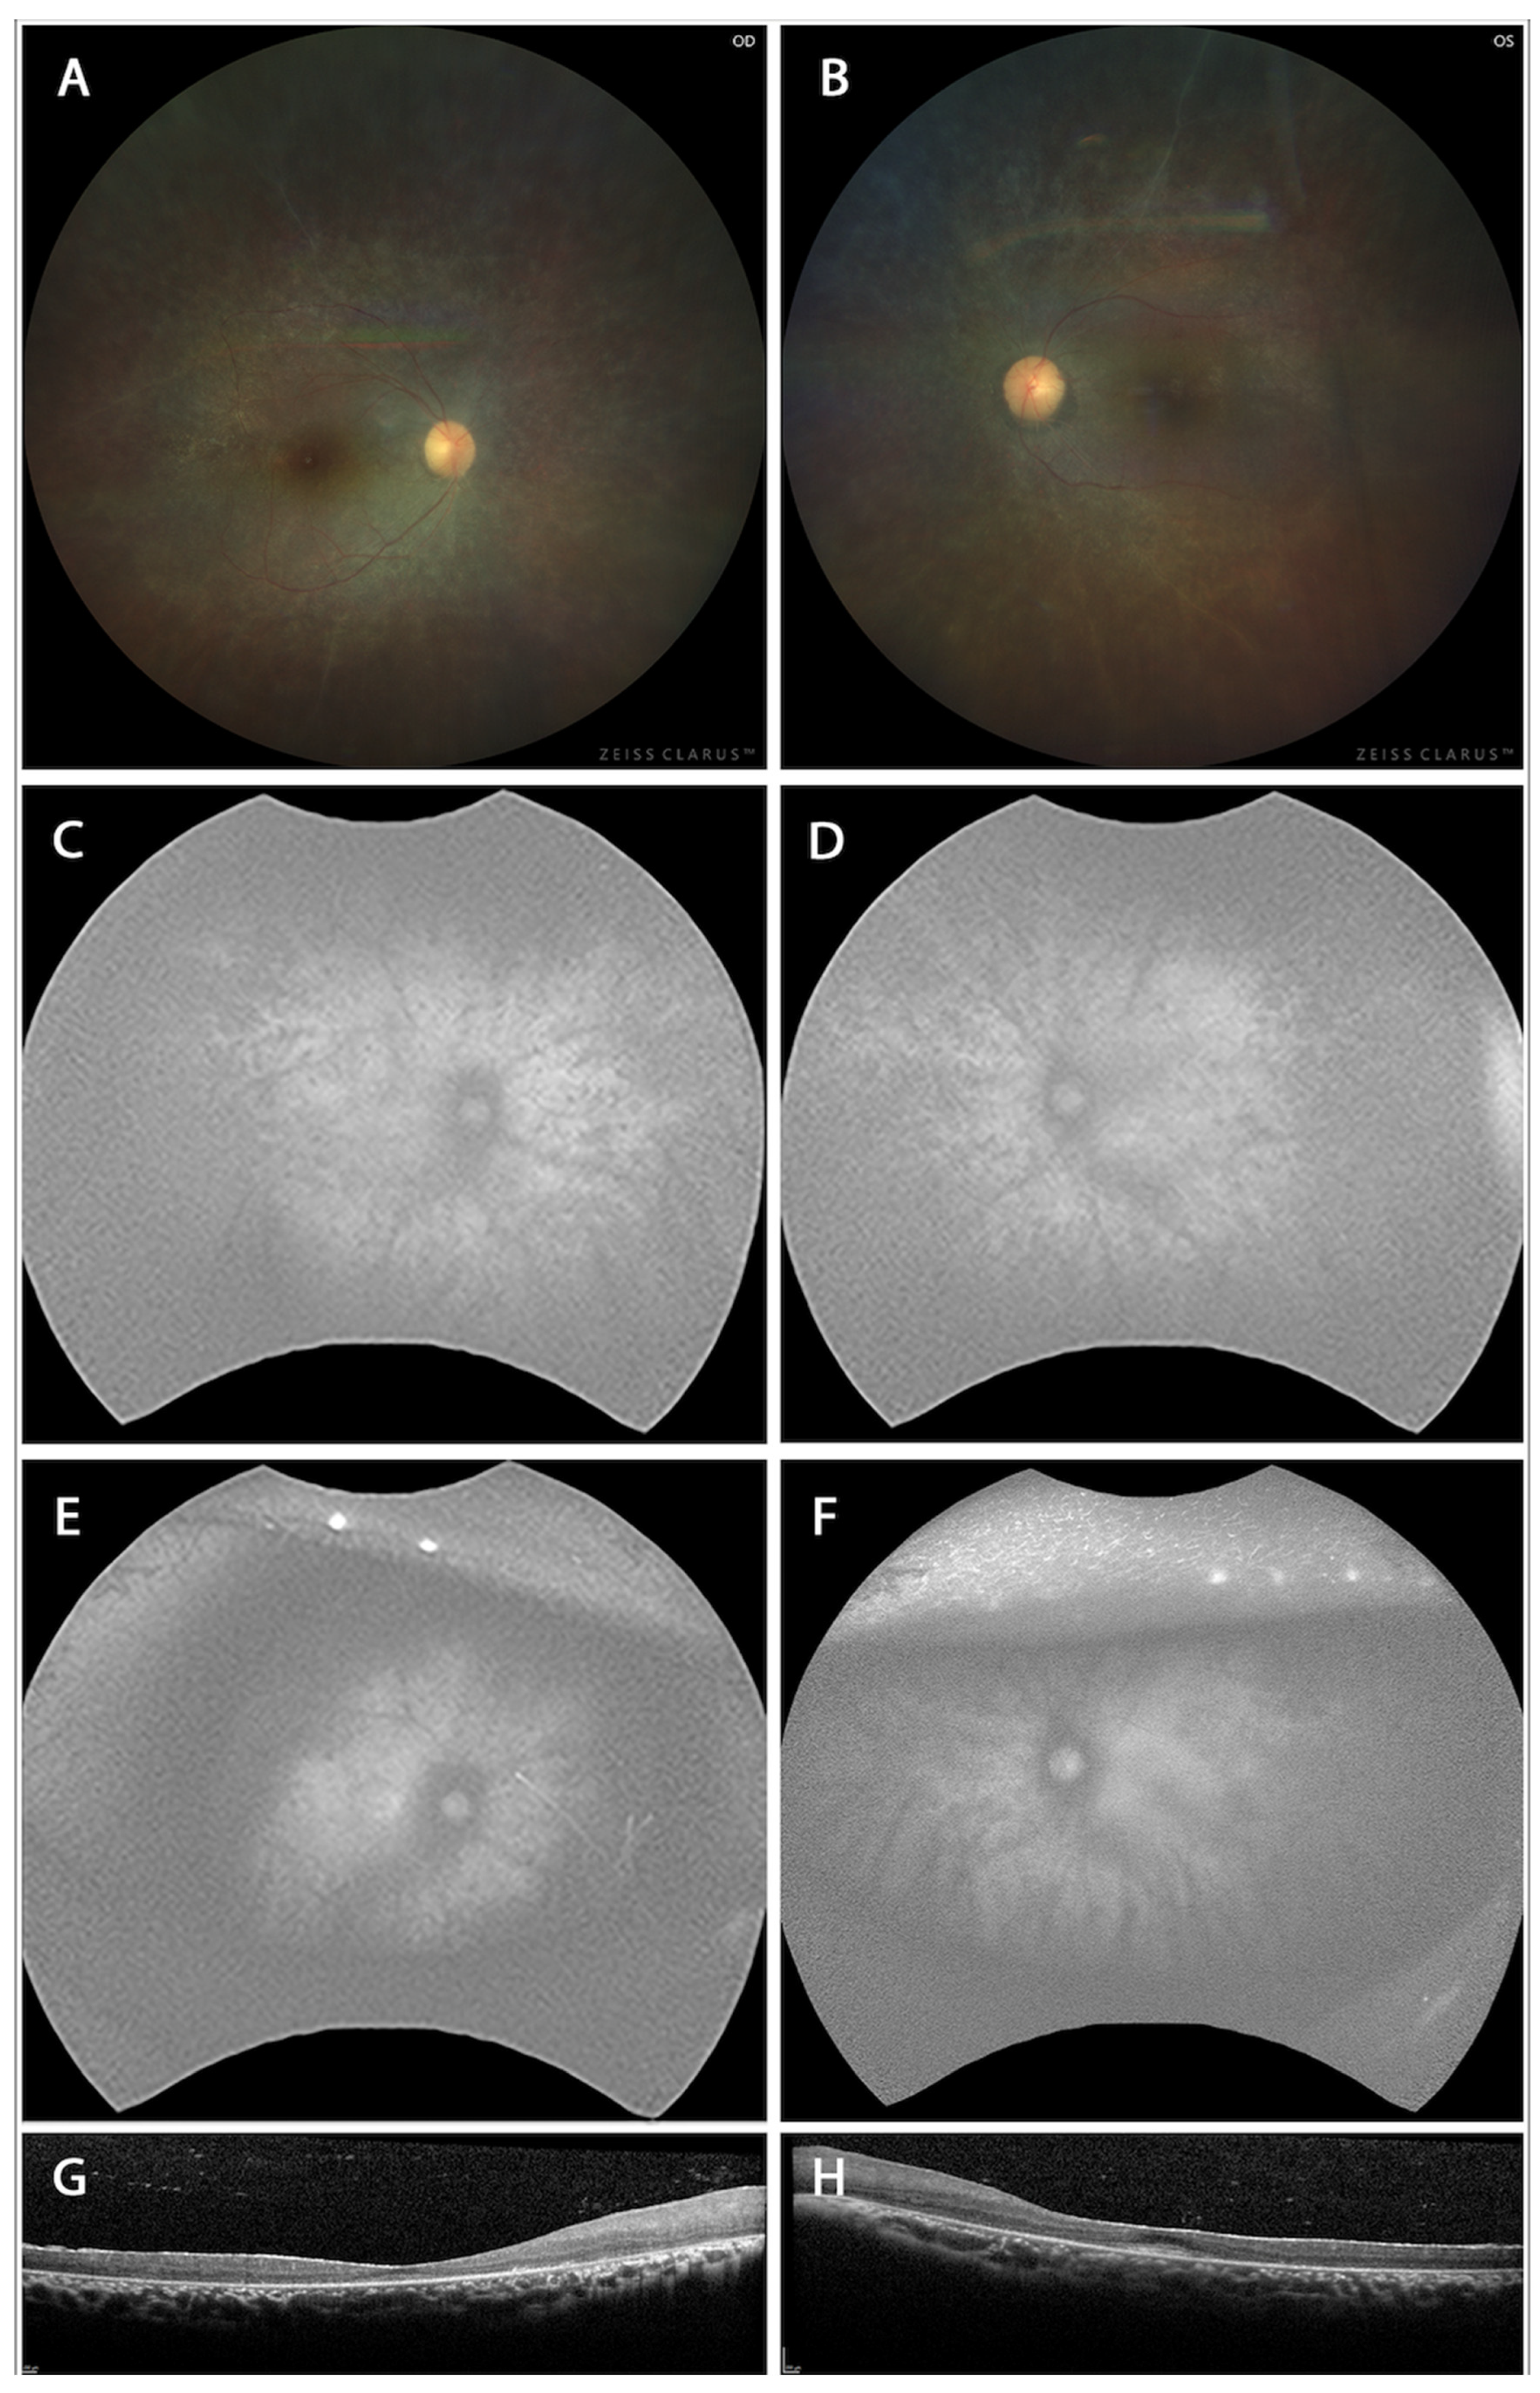

Color fundus photographs in Figure 1 are derived from two unrelated patients known to harbor the PITPNM3 V367M mutation, confirmed by Sanger sequencing of genomic DNA. These images are intended to serve as clinical comparators for the phenotypes observed in our genetically engineered mouse model. Color fundus photographs of human patients (Figure 1A,B) revealed optic discs with mild pallor, generalized narrowing of retinal arterioles, and a peripheral granular, mottled appearance with subtle pigmentary changes. Notably, classic “bone spicule” pigmentation was absent, and the macula displayed relative sparing with loss of the normal foveal reflex. These features align with a rod-cone dystrophy such as retinitis pigmentosa sine pigmento, where the absence of bone spicules signals an early or atypical disease stage.

Fundus autofluorescence (FAF) images of the right (Figure 1C,E) and left (Figure 1D,F) in patients demonstrated a widespread, speckled hypoautofluorescence pattern radiating from the posterior pole to the periphery. Central macular autofluorescence was relatively preserved, encircled by an abnormality ring, and the pattern demonstrated symmetry between the eyes. These findings point to widespread RPE dysfunction or atrophy characteristic of panretinal dystrophy, but with spared central vision. In the PITPNM3 mouse model, both heterozygous and homozygous mutants maintained comparable quantitative autofluorescence (qAF) levels to wild-type controls early on, reinforcing the notion that RPE pathology in mice develops gradually and may require longer observation for overt changes to manifest.

Spectral-domain OCT of the right (Figure 1G) and left (Figure 1H) disclosed thinning of the retinal layers, especially the outer retina, and loss or attenuation of the ellipsoid zone beyond the foveal center. Importantly, the foveal contour was preserved, and there was no evidence of cystoid macular edema or subretinal fluid. Such findings are common in inherited retinal degenerations and reflect progressive photoreceptor loss with central preservation in early to moderate stages.

Figure 1. Color fundus photographs of the right (A) and left (B) eyes show optic disc pallor, generalized attenuation of retinal arterioles, and a granular, mottled appearance of the peripheral retina with subtle pigmentary changes. Fundus autofluorescence (FAF) images of the right (C,E) and left (D,F) eyes at two time points demonstrate a widespread, speckled pattern of hypoautofluorescence extending from the posterior pole to the mid-periphery suggest. Spectral-domain optical coherence tomography (SD-OCT) of the right (G) and left (H) eyes reveals thinning of the outer retina with attenuation or loss of the ellipsoid zone outside the foveal center.